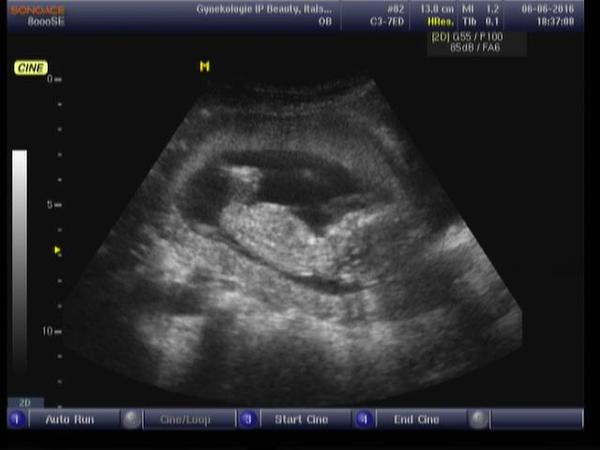

Je to holčička nebo chlapeček? Foto ultrazvuku

Ahoj maminky a budoucí maminky 😉 Prosím, poradila byste mi některá, co vidíte na fotce z ultrazvuku ve 20. týdnu za pohlaví? Určitě jste foteček viděly už mraky, proto vás žádám o radu...Nechci nikoho ovlivnit, proto svůj tip řeknu později 🙂 Děkuju moc!!!

A pupeční šňůra by takhle nebyla vidět? 🙂 kdybyste některá měla taky takovou fotku, prosím nedaly byste si ji sem? 🙂

@barbucha123 mam tahle jen fotku holcicky a je tam videt jasne kavove zrnko. Todle je opravdu klucina u maleho jsme to taky nela takhle vidět ale tu fotku nemuzu uz najit